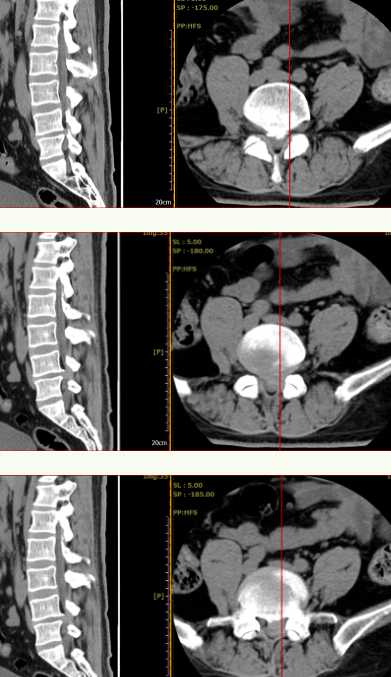

术前CT见:腰4/5椎间盘巨大凸出向后下方,左侧旁中央及侧隐窝狭窄明显,伴腰4、5椎体后缘钙化。

腰椎MRI见:腰4/5椎间盘变性,椎间盘巨大突出,硬膜囊受压明显,左侧椎间孔明显狭窄,左侧神经根受压明显。